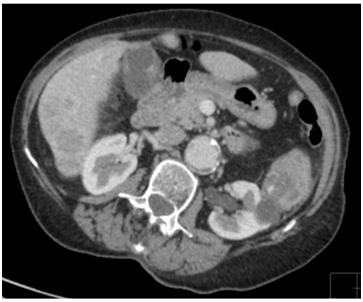

Three months later, she was presented to her general practitioner with vaginal bleeding and was evaluated in two weeks at the Gynecology clinic where on examination, a craggy 2-3cm mass, replacing the left Bartholin’s gland in the lower 1/3rd of vagina and vulva, was noted. This mass was biopsied which showed metastatic clear cell renal carcinoma. On a repeated contrast-enhanced staging CT chest, abdomen and pelvis, progression of her metastatic disease with an increase in the size of her left renal lesion to 7cm was observed (Figure 3&4). The patient was also noted to have become progressively thrombocytopenic. She was therefore, continued on the palliative care pathway with supportive treatment. At the time of submission of this article, patient was still alive under the care of the Oncologists who had discussed and commenced palliative Pazopanib at a reduced dose of 400mg daily. The patient’s main issue was bilateral lymphedema with not much symptoms from her vulvo-vaginal metastases.

Figure 3: Staging CT chest, abdomen and pelvis showing left renal lesion in December 2015.